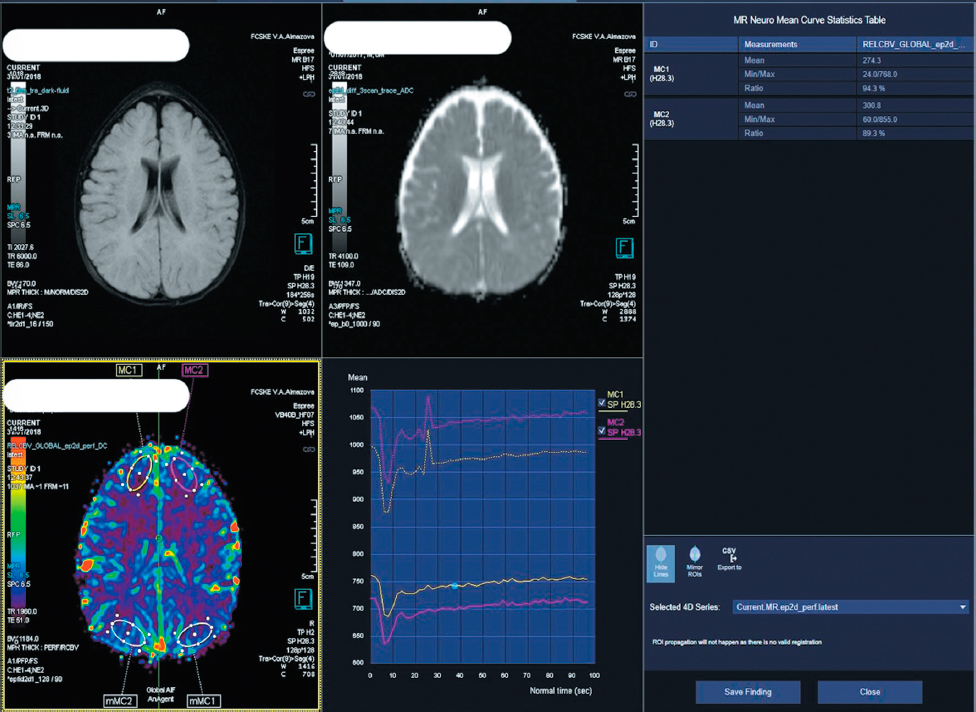

Color-coded perfusion maps of CBF and CBV were generated using the syngo.via software platform (Siemens). Then, regions of interest (ROIs) corresponding to the most compressed cortico-subcortical areas were manually delineated. Subsequently, a mirrored ROI was placed on the contralateral (“unaffected”) side for comparison of MR signal intensity. The perfusion index within the compressed area was calculated relative to the intact region as 100% (Fig. 1).

Fig. 1. CBV perfusion map in a patient with metopic synostosis. Relative perfusion indices are indicated by arrows.